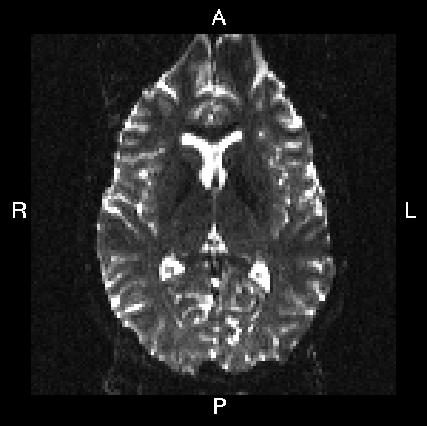

Here is a visual "cheat sheet" for what to put into your --acqp file

| What you see in FSLeyes |

![]() |

|---|---|---|---|---|

| First three columns in --acqp file | 0 1 0 | 0 -1 0 | 1 0 0 | -1 0 0 |